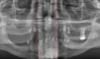

Label the following image:

1. red: nasal cavity

2. green: conchae

3. yellow: nasal septum

A: maxillary sinus

B: mandibular canal

C: internal oblique ridge

D: genial tubercle & lingual foramen

E: submandibular fossa

F: zygomatic process

G: nasal septum

H: anterior nasal spine